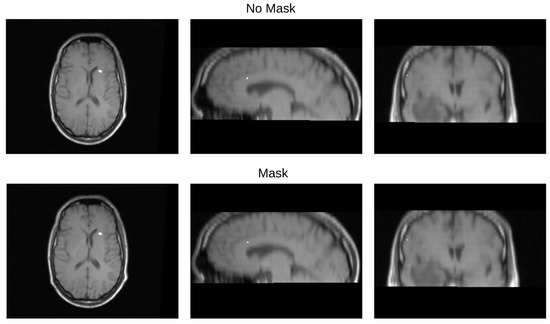

We validated the performance of the fusion method following the two methodologies in Section 3. We used eight pairs of CT and MRI from the RIRE dataset for the first method. The CT images were generated with the method described in Section 3.1.1. We compared the procedure shown in Figure 8 against a fusion procedure that does not employ a sampling mask of the brain tissue, which is shown in Figure 9. Both methods used a rigid registration with MI as the similarity metric and gradient descent for the optimization. We used descriptive statistical metrics of central tendency and variation to compare the methods using the validation from Section 3.1. These results were summarized in the box plot shown in Figure 10. For the second validation, we faced a limitation in the number of images available for evaluation. Given this constraint, we opted to compare the methods individually for each of the four cases. A scatter plot was chosen as the most suitable representation to visualize the error dispersion for both methods. Scatter plots are particularly effective in such scenarios as they allow for clear visualization of individual data points, making it easier to discern patterns or anomalies, especially when dealing with a smaller dataset. This approach provides a more transparent and detailed view of the distribution of errors across the limited set of images. The results of this comparison are illustrated in Figure 11.

Table 3 displays the Euclidean distance between the reference points and the resulting points of the transformation from the compared methods. From the data, we can observe that the difference in the Euclidean distance for our method is significantly lower in images 3, 6, and 8. This is mainly caused by the differences in the original images that have some variations in brain tissue, as shown in Figure 12, Figure 13 and Figure 14. Due to some electrodes passing through these areas with variations, the sampling in the registration does not use these voxels to compute the transformation, thus improving the registration when the mask is used. The results are represented in Figure 10, where our method using a sampling mask yields a Euclidean distance of 1.3176 mm with a standard deviation of 0.8643. In contrast, the method without a sampling mask yields a Euclidean distance of 1.2789 mm with a standard deviation of 5.2511. These findings suggest that the use of the mask improves the registration when there is a great difference in the tissue between the MRI and CT images due to the reduction in voxel sampling of these varying tissues in the registration process.

Figure 14. Image 8 fusion with no mask and with a mask.

Diagnostics 13 03420 g014